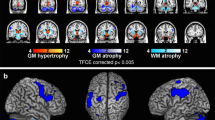

In a previous study [7], investigating brain tissue integrity by means of voxel-based morphometry (VBM) and T1-weighted/T2-weighted (T1w/T2w) maps, a whole-brain voxel-level analysis revealed reduced volume in bilateral putamen and cerebellar gray matter (GM), reduced white matter (WM) volume in the cerebellum and brainstem, and increased mean regional values of T1w/T2w in bilateral putamen in MSA patients compared to both Parkinson’s disease (PD) patients and healthy controls (HC). Specifically, the ratio of the signal intensity of the T1-weighted and T2-weighted (T1w / T2w) MRI images has been used as semi-quantitative measure for myelin content in gray matter and its advantage that images with high spatial resolution can be easily acquired without complex modeling, during routine clinical examination [7].

Regional mean values of each parameter (GM, WM and T1w/T2w) at each time point were calculated in each cluster binary masks obtained in the voxel-level analysis of our previous study [7] performed on the baseline data. Particularly, regional cluster values in bilateral putamen, cerebellar GM, and cerebellar/brainstem WM were considered as region of interest in the present study.

At T0, CA was directly related to GM density in the cerebellum/brainstem (rho = 0.43; p = 0.03), WM density in the cerebellum/brainstem (rho = 0.40; p = 0.04), and T1w/T2w (WM) in the cerebellum/brainstem (rho = 0.56; p = 0.01). There was a negative correlation between GM density in the right putamen and TMT-A (rho = − 0.40; p = 0.04). After correction for multiple comparisons, only correlation between T1w/T2w (WM) in the cerebellum/brainstem and CA was retained (Table 2).

Logistic regression analysis showed that age (β = − 9.45, p = 0.02) and T1w/T2w value in the Left putamen (β = 230.64, p = 0.01) were significant predictors of global cognitive status at T0, explaining 65% of the variance (R2 = 0.65).

At T1, we calculated changes in neuropsychological scores and MRI parameters between T1 and T0. After correcting for multiple comparisons, a positive correlation was found between ∆-values of the GM density right putamen and words repetition E.N.P.A. test (rho = 0.47; p = 0.02). There was a negative correlation between ∆-values of the T1w/T2w (WM) cerebellum/brainstem and TMT-A (rho = − 0.55; p = 0.01) (Table 3). In the group of patients worsening at T1, negative correlations were found between ∆-values of the GM density in the right putamen and TMT-A (rho = − 0.50; p = 0.03), and between ∆-values of the GM density in the Left putamen and non-words repetitions E.N.P.A. test (rho = − 0.48; p = 0.04). There was a positive correlation between ∆-values of the GM density in the right putamen and word repetition E.N.P.A. test (rho = 0.48; p = 0.04). Moreover, a trend towards significance was found for the following correlation: ∆-values of the T1w/T2w in the cerebellum/brainstem GM and CA (rho = 0.49; p = 0.05) (Table 3).

Logistic regression analysis showed that ∆-values of WM density in the cerebellum/brainstem (β = 2188.70, p = 0.02) significantly predicted cognitive worsening at T1, explaining 64% of the variance (R2 = 0.64).